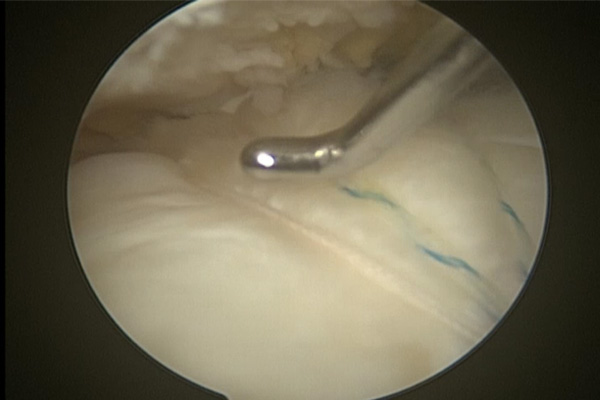

REPARACIÓN DE MANGUITO ROTADOR CON SUTURAS Y ANCLAJE